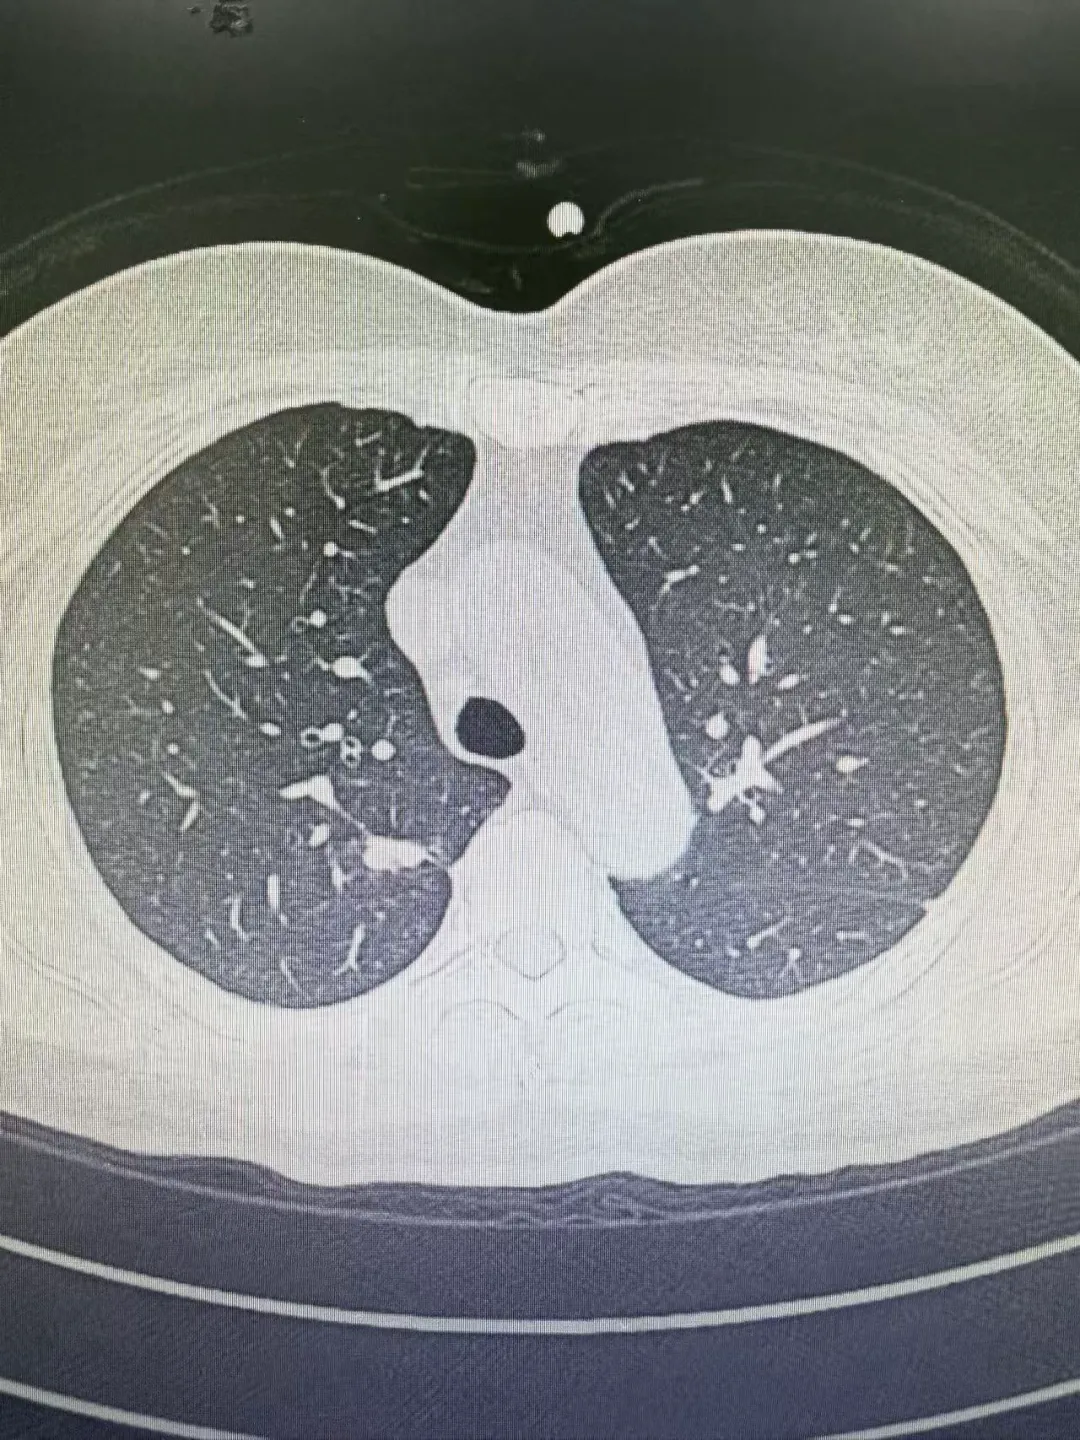

病例2:

患者伦某,因胸闷、憋气1月就诊于我院老年医学科,行胸部CT检查示右肺上叶后端结节,考虑恶性可能性大,随转入我科。在拟上手术前一天,经张振江主任阅读病史及综合分析后考虑结节存在良性可能,果断终止手术,后行穿刺诊疗,确诊为良性结节。随访至今略有缩小。

2025.06.27 胸部CT